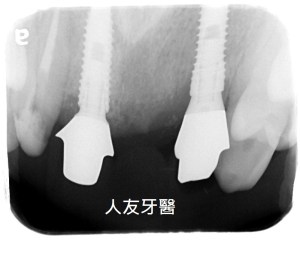

舊式門牙牙橋拆除、植牙案例分享